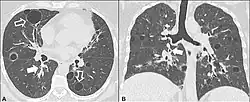

| CT scan of the lung showing bullae in the lower lung lobes of a subject with type alpha-1-antitrypsin deficiency. There is also increased lung density in areas with compression of lung tissue by the bullae. | |

A focal lung pneumatosis is an enclosed pocket of air or gas in the lung and includes blebs, bullae, pulmonary cysts, and lung cavities. Blebs and bullae can be classified by their wall thickness.[1]

- A bulla has a wall thickness of less than 1 mm.[2] By radiology definition, it has a total size of greater than 1 cm.[3] By pathology definition, it originates in the lung parenchyma (rather than in the pleurae).[4]

- Alpha 1-antitrypsin deficiency[6]